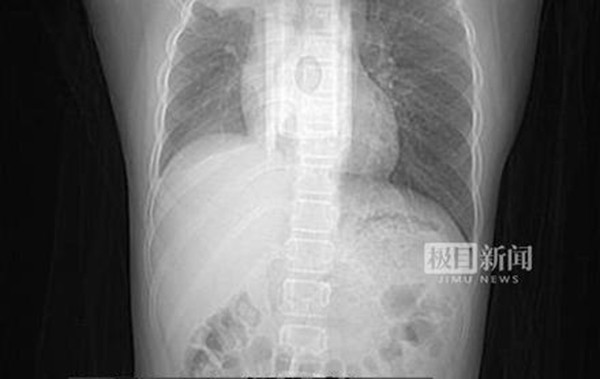

Phổi bé trai nổi nhiều mảng trắng.

Sau một loạt các cuộc kiểm tra, bác sĩ nhận định rằng, tình trạng của Zhou Zhou đã phát triển thành viêm phổi. Từ những bức ảnh siêu âm có thể thấy một bên mô phổi của cậu bé có một mảng trắng lớn.